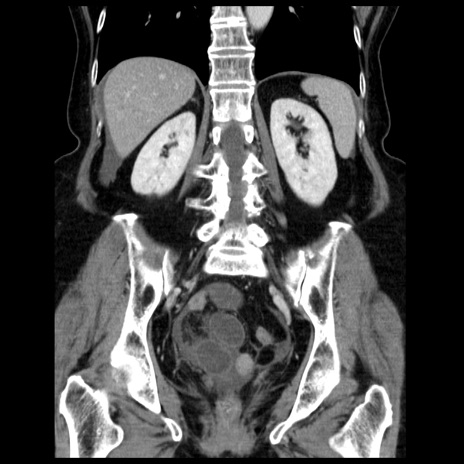

症例13(冠状断像)

【症例】70歳代女性

【主訴】腹痛、嘔吐

【現病歴】15時間程前(昨晩)より腹痛あり。今朝になっても症状の改善なく、嘔吐あり。腹痛も増悪あり、救急外来受診。

【既往歴】子宮癌全摘術後

【身体所見】意識清明、BP 121/72mmHg、P 74bpm、SpO2 100%(RA)、腹部:平坦・軟、腸雑音ほぼ聴取せず。下腹部・心窩部・臍左上に圧痛あり。反跳痛なし。

【データ】WBC 10600、CRP 0.15